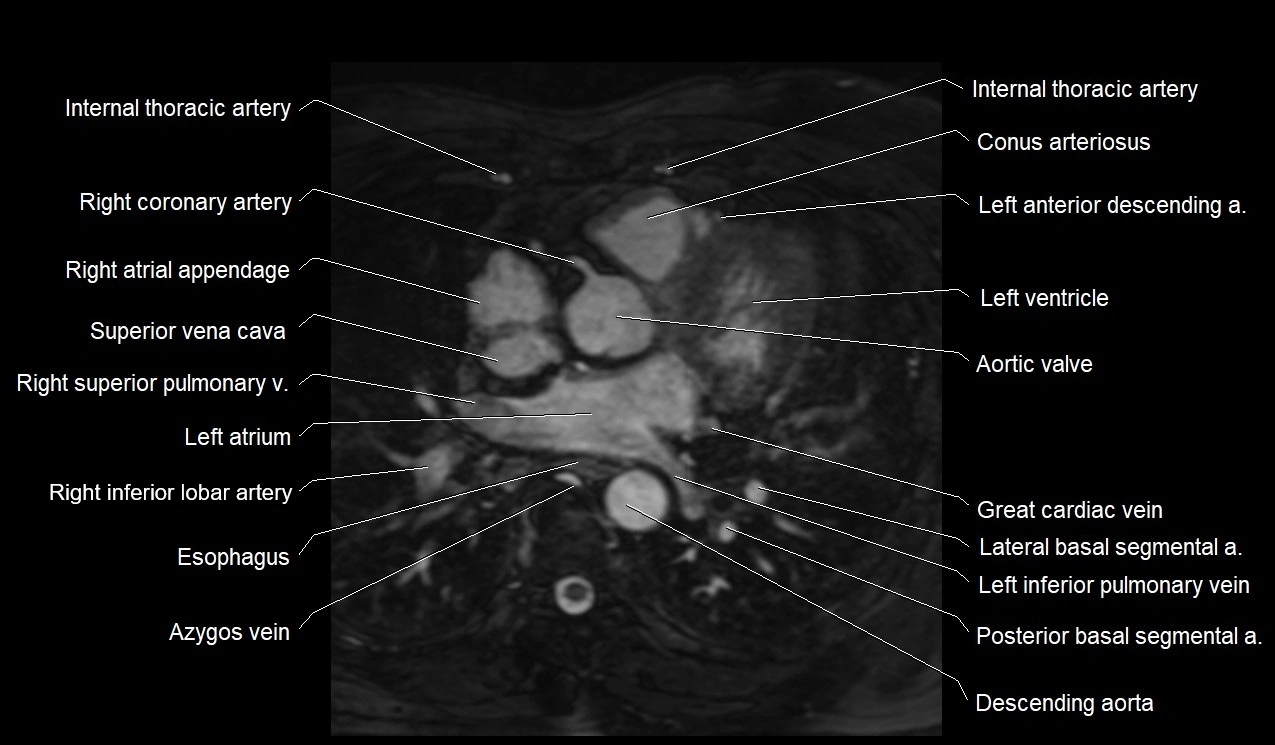

MRI image